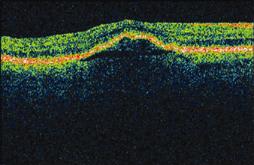

I found the test to be reliable based on indices of false negative and false positive results. After a follow-up OCT confirmed the presence of a pigment epithelial detachment (PED) (Figure 2), I discussed with the patient treatment versus observation. Since PEDs are unpredictable and may be stable for a long time, we elected to watch for now. Upon her return visit after 1 month, her vision had dropped from 20/40 to 20/80 and repeat OCT revealed a larger PED (Figure 3). At that time we instituted Lucentis for the right eye as well. Thus far, she has had a total of seven Lucentis injections, two pegaptanib (Macugen, OSI Pharmaceuticals) injections, one PDT, and two Avastin (Genentech) injections. As of July 2008, the date of her last injection, her vision was stable at 20/60. I believe the information generated by the Foresee PHP saved her sight by picking up her lesion much earlier, allowing me to treat promptly.

Figure 2. Mild pigment epithelial detachment (PED).

Figure 3. Much larger PED after 1 month.